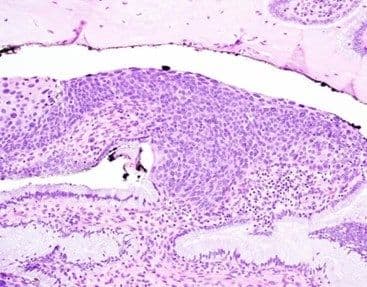

Squamous cell carcinoma is the most common histological subtype of cervical cancer. Squamous cell carcinoma of the cervix is most commonly linked to HPV 16 infection, although multiple other high-risk HPV serotypes are also associated with squamous cell carcinoma, including HPV 18, 31, 33, and 45, among others.  Grossly, tumors may be firm indurated masses, polypoid, or ulcerated. Histologically, squamous cell carcinoma appears as infiltrative sheets and irregular nests of angulated to round cells with coarse chromatin and nucleoli (Figure 8A, 8B). Necrosis is common [76].

Figure 8

Pronounced desmoplastic stromal reaction may be visible around cell nests (Figure 9A, 9B, arrow). Lymphovascular space invasion may also be present, especially in more deeply invasive carcinomas.

Figure 9